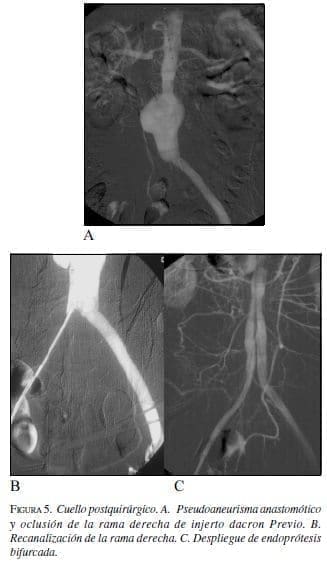

• Posquirúrgico:

Las dilataciones que se producen entre las arterias renales y una prótesis ya implantada quirúrgicamente en general no tienen cuello, lo cual sería una limitación. Pero el sólo recubrimiento de la pared impide que el flujo choque directamente sobre la pared arterial y sí sobre el injerto, hace esto que sea una indicación para evitar la progresión del segmento dilatado (figura 5).